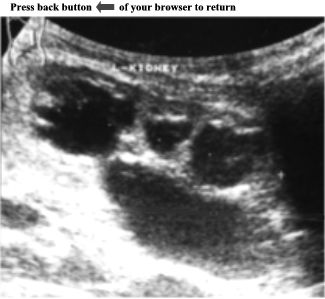

CASE

5:

Ultrasound

examination

of

an

asymptomatic

adult

patient.

Left

kidney

is

enlarged

and

shows

numerous

anechoic

areas

in

the

cortex

medulla.

These

vary

size

their

margins

are

irregular.

largest

one

measures

3.3cm

X

1.6cm.

Further

reveals

right

as

well.

ANSWER:

Polycystic

Disease